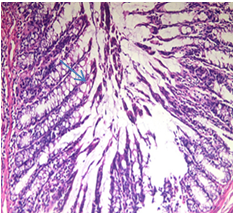

Colonic sections from control group revealed typical architecture of colon tissue (fig. 7 a).

a) Normal Control: Normal architecture of the mucosa (x40)

b) DSS colitis rats: Cryptitis, crept branching and distortion (x100)

c) Sulfasalazine treated group: Normal mucosa and mild glandular reparative changes (x40)

Fig. 7: Photomicrographs of colon tissue sections (H and E)

On the other hand, Colons of the DSS group indicated ulceration with inflammatory cell infiltration (fig. 7 b) However, colons of the sulfasalazine treated group displayed nearly normal histological structure (fig. 7 c)

The present study verified the comparative evaluation of sulfasalazine’s pharmacological efficacy in the rat model of UC. As shown in fig. 7 DSS group demonstrated inflammatory cell infiltration edema and lining mucosal epithelium desquamation. These findings may be due to the direct lethal effect of DSS resulting in breakdown of the mucosal epithelial barrier. Our findings were in line with other earlier reports [19]. Treatment with sulfasalazine ameliorated histopathological changes. As shown in table 1, the DSS control group displayed significantly reduced cAMP and increased LRG, MPO and TNF-α as compared with the normal group. Results from previous studies showed that the level of MPO and TNF-α was increased with the seriousness of experimental colitis [20-21].